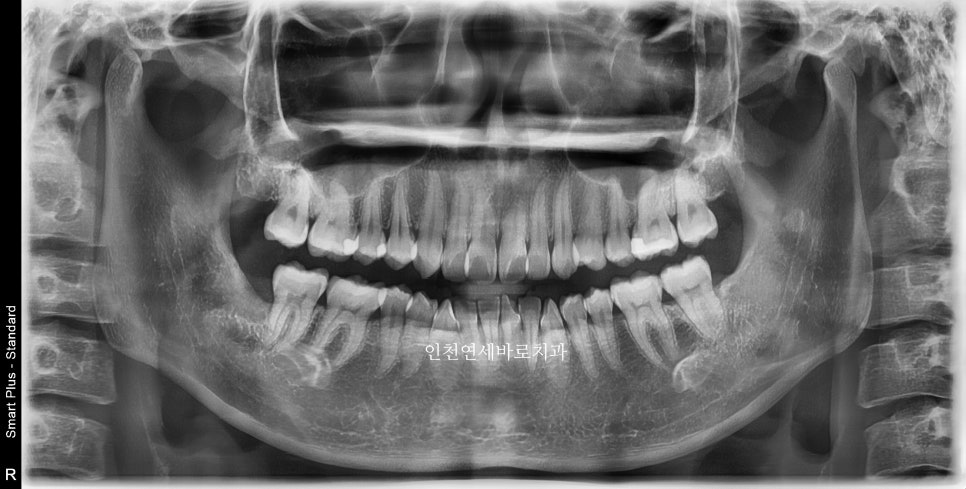

첫 내원 23.12.23.

이후 한달의 제작기간 후 24년 2월초에 시작한 환자분입니다.

삐뚤삐뚤한 앞니를 고치고 싶어오셨습니다

인비절라인 라이트 치료 계획

인비절라인 라이트로 진행하기로 하고 장치 제작을 했습니다.